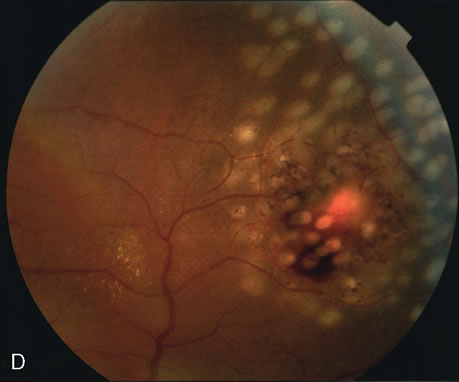

Clinically discernible peripheral dependent bullous neurosensory detachments have been described in patients with chronic CSC.85–92 Yannuzzi and co-workers first characterized the presence of RPE atrophic tracts extending inferiorly in the fundus periphery secondary to antecedent retinal detachment in patients with CSC.85 Presumably, there is a particularly severe and/or longstanding leakage of fluid from an RPE defect in the subretinal space at the posterior pole. The subretinal fluid gravitates inferiorly to form a dependent neurosensory detachment in a “flask,” “teardrop,” “dumbbell,” or “hourglass” pattern (Fig. 31). Sometimes the tract of subretinal fluid connecting the macular detachment with the bullous neurosensory detachment in the inferior hemisphere is so shallow that it is very difficult to appreciate. The RPE under the chronic retinal detachment experiences atrophic changes that appear as atrophic RPE tracts connecting the posterior pole with the dependent retinal detachment. The retina itself develops secondary manifestations including pigment migration, capillary dilatation (telangiectasia) proximally and capillary nonperfusion (ischemia) distally to the area of detached retina (see Fig. 31). The changes in the RPE consist of both RPE atrophy and pigment clumping in the form of perivascular deposits or bone spicules, a condition described by Gass as a “pseudoretinitis pigmentosa–like atypical CSC presentation.”87

Fig. 31. A 47-year-old woman with an18-year history of central serous chorioretinopathy in both eyes. A. Color photograph composite of the left eye shows bullous dependant detachment of the neurosensory retina inferiorly. B. Fluorescein angiogram composite reveals diffuse decompensation of the retinal pigment epithelium, multiple scattered pigment epithelium detachments 9PEDs), and obliteration of the retinal capillaries in the region of the detachments. Note the presence of early neovascularization at the junction between perfused and non-perfused retina. C. Clinical photograph of the left eye shows PED superior to the optic disc partially surrounded by fibrin deposits. D. Fluorescein angiography confirms the presence of active leakage from the serous PED. E, Color photograph composite of the same eye 2 months after laser treatment of the site of leakage reveals partial resolution of the detachment and lipid precipitation. F. Clinical photograph composite 16 months after the laser treatment in the area of the leakage shows complete resolution of the detachment and partial reperfusion of the inferior retina.